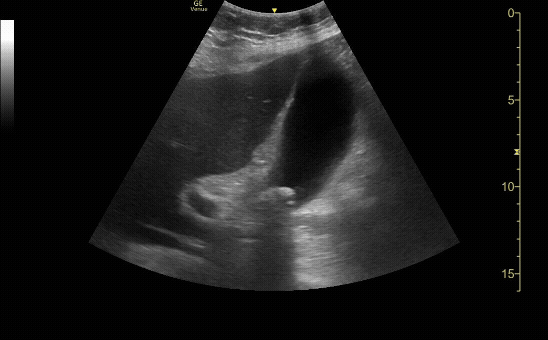

Gallbladder in short view

c/o Kristina Pfieffer, MD